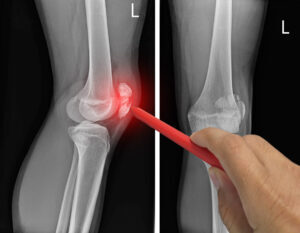

تشخیص نرمی کشکک زانو

تشخیص نرمی کشکک زانو توسط پزشک متخصص ارتوپدی انجام میشود. در اولین مرحله، پزشک از تاریخچه بیماری و علائم شما سوال میپرسد و ممکن است زانوی شما را معاینه کند. برای تشخیص دقیقتر، پزشک ممکن است از آزمایشهای تصویربرداری مانند رادیوگرافی یا MRI استفاده کند. این آزمایشها به پزشک کمک میکنند تا آسیبهای غضروفی و میزان نرمی کشکک زانو را مشاهده کند.